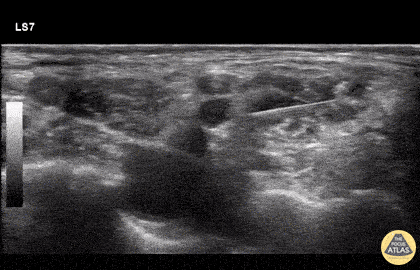

80 y/o intoxicated female found down with L shoulder dislocation. In order to avoid opiates/sedatives, inter-scalene block was done to facilitate reduction. http://highlandultrasound.com/interscalene-block - for more on technique Dr. Forrest Andersen - Denver Health Emergency Medicine